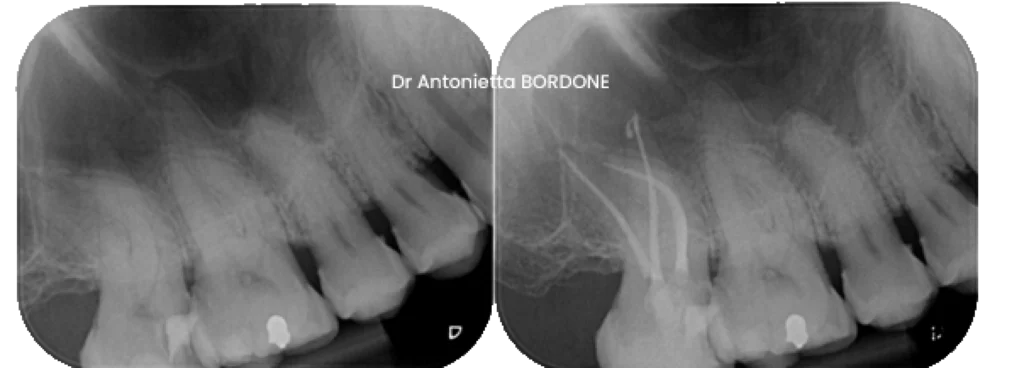

Exemple de traitement canalaire initial d’une molaire en pulpite irréversible :